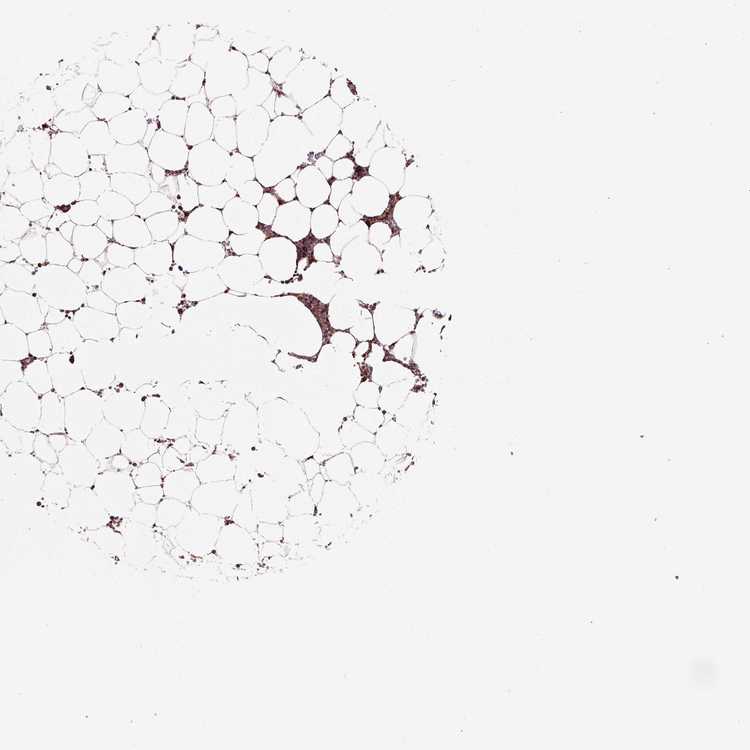

BONE MARROW - Antibody stainingi

Antibody staining in the annotated cell types in the current human tissue is reported as not detected, low, medium, or high, based on conventional immunohistochemistry profiling in selected tissues. This score is based on the combination of the staining intensity and fraction of stained cells.

Each image is clickable and will lead to virtual microscopy that enables deeper exploration of all samples and also displays staining intensity scores, fraction scores and subcellular localization as well as patient and tissue information for each sample.

Antibody HPA018126Antibody HPA063617

Hematopoietic cells HighHigh